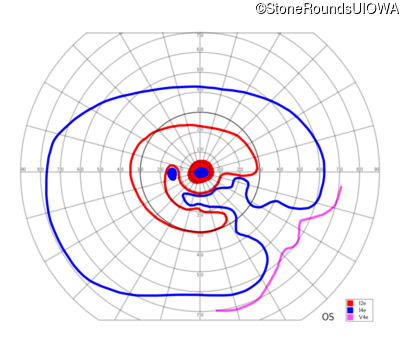

AR Stargardt Disease (IIA)

AR Stargardt Disease (IIA)

| Age at visit: 12 years |

| Age at visit: 13 years |

| Age at visit: 15 years |